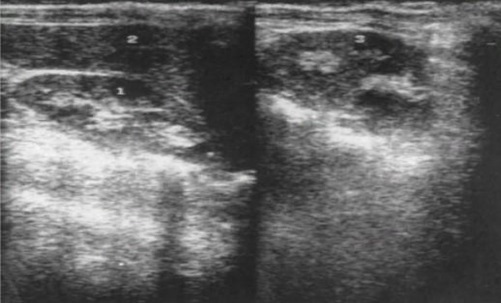

2.2. УЗИ почек от 16.10.2022 г.: заключение: ультразвуковые признаки уплотнения чашечно-лоханочной системы, повышения эхогенности и истончения паренхимы обеих почек, нарушения и изменения оттока мочи из обеих почек на момент осмотра не выявлено. Одиночные субкапсулярные, интрапаренхиматозные и парапельвикальные кисты обеих почек (рис. 2).

Рис. 2. Ультразвуковое исследование почек: 1 – правая почка, 2 – печень, 3 – левая почка.